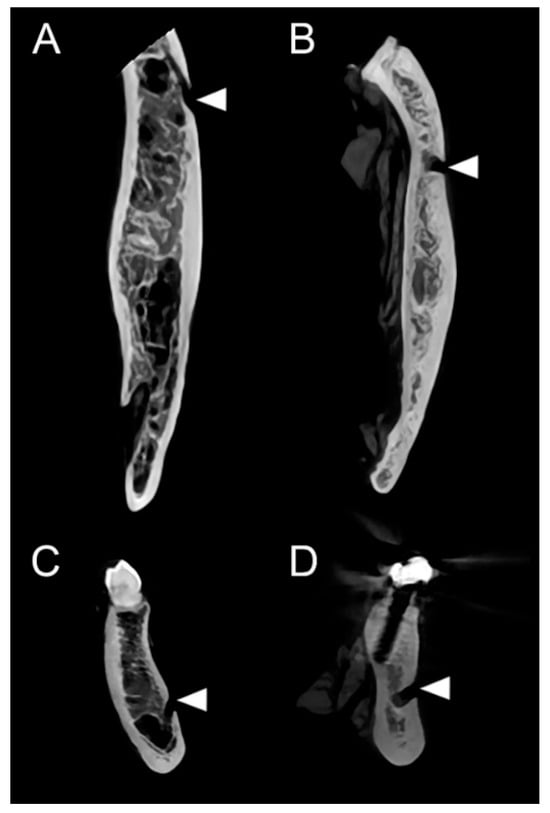

3.2. CBCT-Based Analysis of Mental Canal Opening Direction